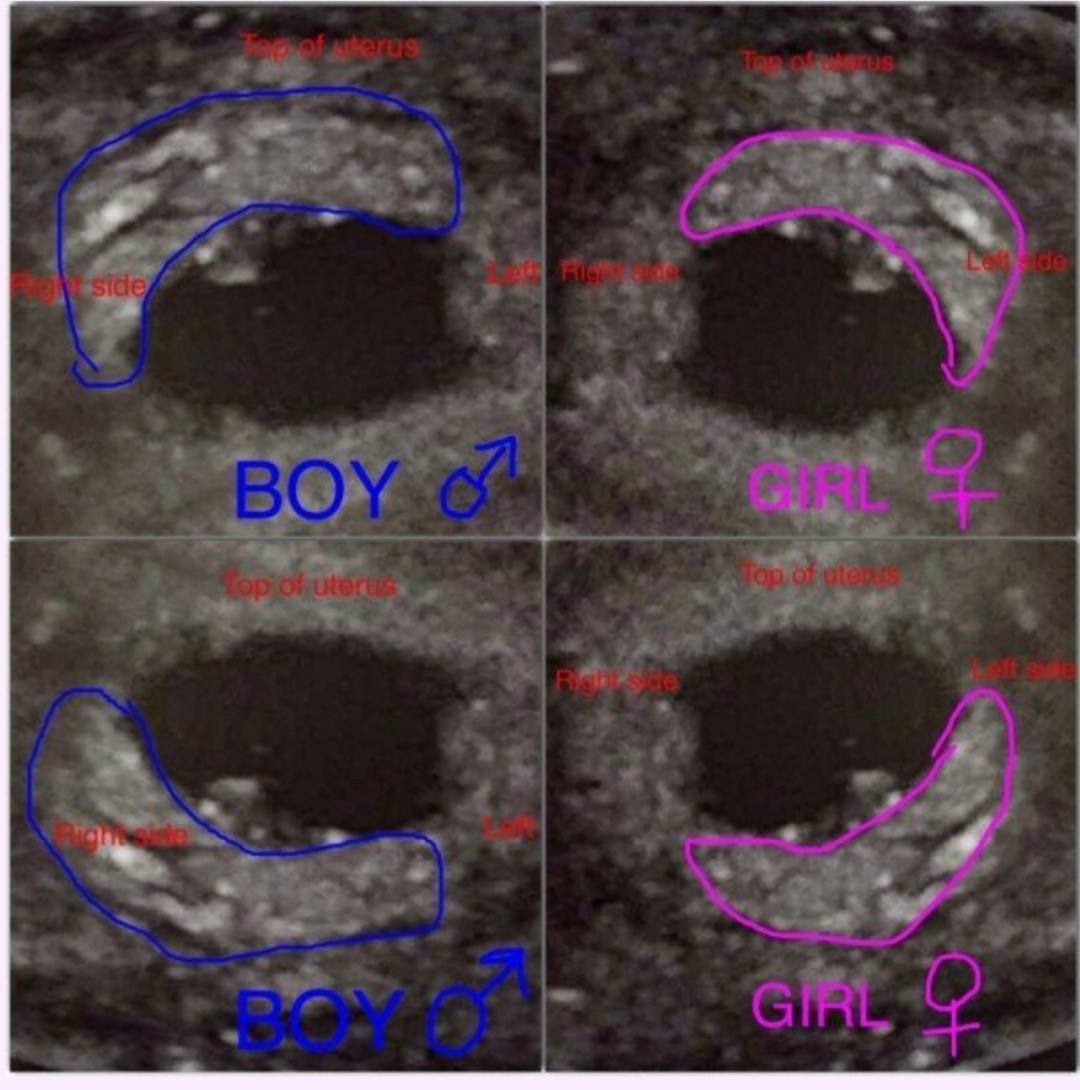

Ja też już jestem po wszystkim. Termin na 10.07. Serduszko bije 171x/min, cale1,74cm człowieka. Następna wizyta 22.12, prenatalne 28.12. I co ten ramzi mowi, dalej dziewczynka? :D

Tak mówi Ramzi ktoś kiedys pisał mi że po moim zdj widzi chłopca a ja tu dziewczynkę widze